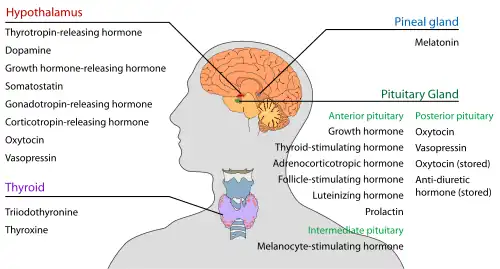

The hypothalamus (pl.: hypothalami; from Ancient Greek ὑπό (hupó) 'under' and θάλαμος (thálamos) 'chamber') is a small part of the vertebrate brain that contains a number of nuclei with a variety of functions. One of the most important functions is to link the nervous system to the endocrine system via the pituitary gland. The hypothalamus is located below the thalamus and is part of the limbic system.[1] It forms the basal part of the diencephalon. All vertebrate brains contain a hypothalamus.[2] In humans, it is about the size of an almond.[3]

The hypothalamus has the function of regulating certain metabolic processes and other activities of the autonomic nervous system. It synthesizes and secretes certain neurohormones, called releasing hormones or hypothalamic hormones, and these in turn stimulate or inhibit the secretion of hormones from the pituitary gland. The hypothalamus controls body temperature, hunger, important aspects of parenting and maternal attachment behaviours, thirst,[4] fatigue, sleep, circadian rhythms, and is important in certain social behaviors, such as sexual and aggressive behaviors.[5][6]

Hormone release

The hypothalamus has a central neuroendocrine function, most notably by its control of the anterior pituitary, which in turn regulates various endocrine glands and organs. Releasing hormones (also called releasing factors) are produced in hypothalamic nuclei then transported along axons to either the median eminence or the posterior pituitary, where they are stored and released as needed.[25]

In the hypothalamic–adenohypophyseal axis, releasing hormones, also known as hypophysiotropic or hypothalamic hormones, are released from the median eminence, a prolongation of the hypothalamus, into the hypophyseal portal system, which carries them to the anterior pituitary where they exert their regulatory functions on the secretion of adenohypophyseal hormones.[26] These hypophysiotropic hormones are stimulated by parvocellular neurosecretory cells located in the periventricular area of the hypothalamus. After their release into the capillaries of the third ventricle, the hypophysiotropic hormones travel through what is known as the hypothalamo-pituitary portal circulation. Once they reach their destination in the anterior pituitary, these hormones bind to specific receptors located on the surface of pituitary cells. Depending on which cells are activated through this binding, the pituitary will either begin secreting or stop secreting hormones into the rest of the bloodstream.[27]

Other hormones secreted from the median eminence include vasopressin, oxytocin, and neurotensin.[29][30][31][32]

In the hypothalamic–pituitary–adrenal axis, neurohypophysial hormones are released from the posterior pituitary, which is actually a prolongation of the hypothalamus, into the circulation.